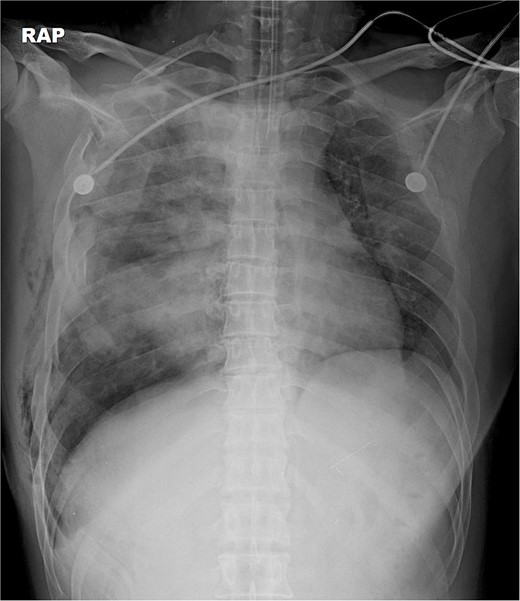

A 31-year-old unconscious male was in an unwitnessed accident when a car hit the motorcycle he was driving. A rescue team transported him to the emergency department. Clinical examination revealed hypoxia with SpO2 at 85%, tachycardia at 126 bpm, hypotension of 69/58 mmHg, and hypothermia at 35.8°C. Initial arterial blood gas analysis (ABGA), pH, PaO2, and pCO2 were 6.92, 49, and 58, respectively. Chest X-ray showed right hemopneumothorax, mediastinal shifting, and multiple bilateral rib fractures (Fig. 1). A right-side closed thoracostomy was performed. The chest drainage of 1 L was bloody. Chest computed tomography (CT) showed fractures in the right ribs 1 to 9 and left ribs 1 to 7, as well as lung contusions, multiple lung lacerations, right hemopneumothorax, and active hemorrhage in the right upper and lower lung lobes (Fig. 2). Brain and abdominopelvic CT showed no organ injury. An emergency thoracotomy was ordered.

Simple radiographs obtained after each operation. (a) Radiograph after the first operation. Gauze, which is visible as a wavy white line, was packed in the right thoracic cavity. Multifocal opacity was seen in the right lung, and there was left upper lung atelectasis. ECMO catheters were placed in the IVC. (b) Radiograph following the second operation. The right ribcage is narrowed due to displaced fractured ribs. (c) Radiograph after the third operation. Five plates were applied to the fractured ribs.